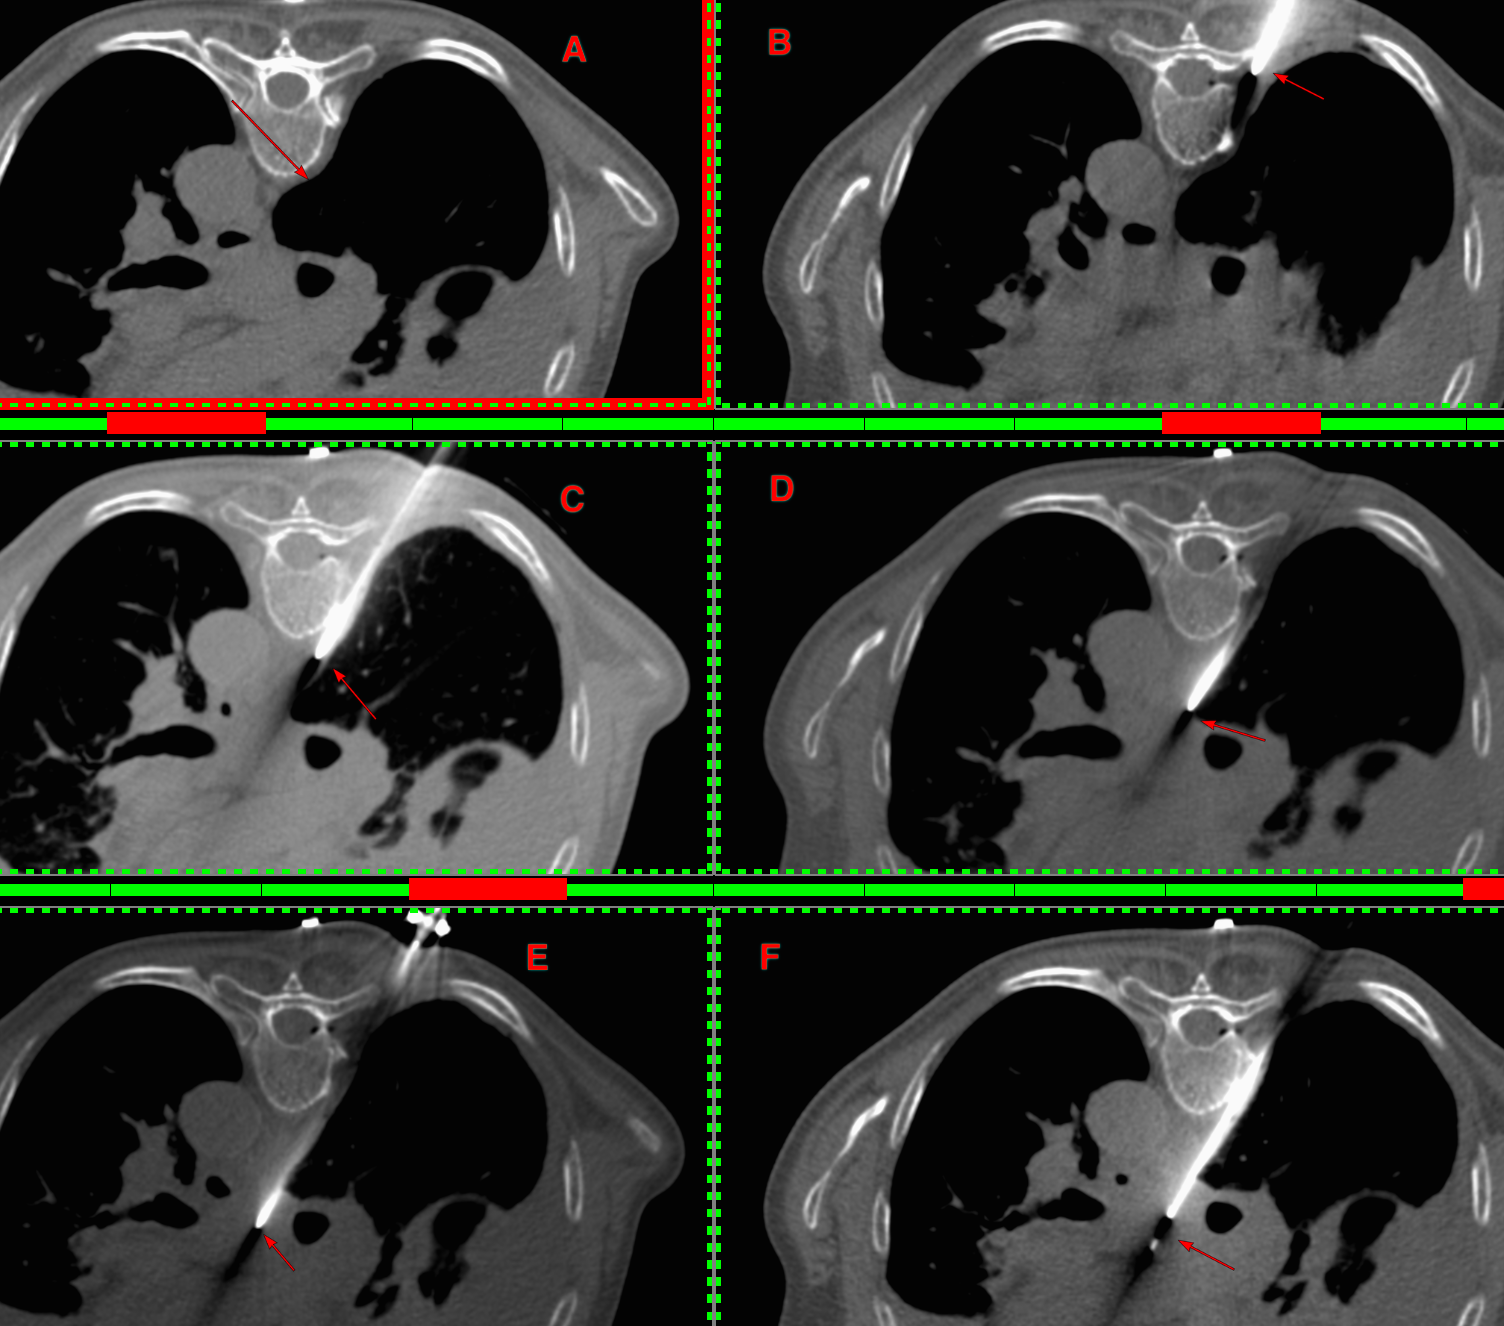

The lung was almost at the midline and there was concern that a transparenchymal approach (A) may be needed as in the last case.

Using an 18G Cook needle, 8 cc of lignocaine was injected in the space between the pleura and foramen in the inter-transverse space (B). Once some space was created then it was advanced with 3 injections of 10-15 cc of a combination of lignocaine and saline (C, D), until the needle tip rested along the posterior margin of the node (D) and then it was pushed into the node (E) followed by the biopsy (F). The gun has a 10 mm throw.

6 cores were obtained for histopath and 1 for microbiology and the final diagnosis was relapse of T-cell NHL.

This again takes off my last post on the transparenchymal approach to paratracheal node biopsies. An extrapleural approach with hydrodissection can usually easily be done and while EBUS is commonly used these days, it is not superior to CT guided biopsy, just non-inferior.

This biopsy took 13 minutes from placing the marker to removing the needle and with preparation, counseling, and post-operative stay of 90 minutes, the entire day-care time was 2 1/2 hours and the patient went home normally.

CT guided biopsies are simpler, easier, quicker and much less expensive than EBUS or similar procedures and while fewer and fewer radiologists are learning these skills, they are well worth the effort even today and for the foreseeable future.